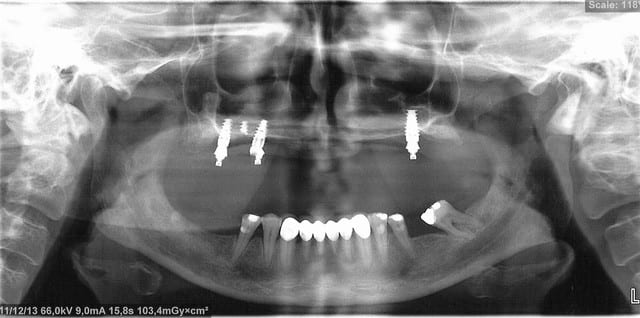

Voici donc les panos pour vos petits yeux ébahis

Profitez bien : elles sont ds l ordre chronologique...

- On y voit un manque flagrant de densité du greffon

- On y voit une perte d'un implant sans changement de plan de traitement, on se retrouve avec un seul implant du coté où mastique le patient

- On y voit une armature qui baille sur le seul implant qui reste secteur 2, et donc manque de passivité

- On y voit ce qui devait arriver,

Mais je vois aucun rapport entre l’échec et la nature du matériau mis en place dans le sinus....